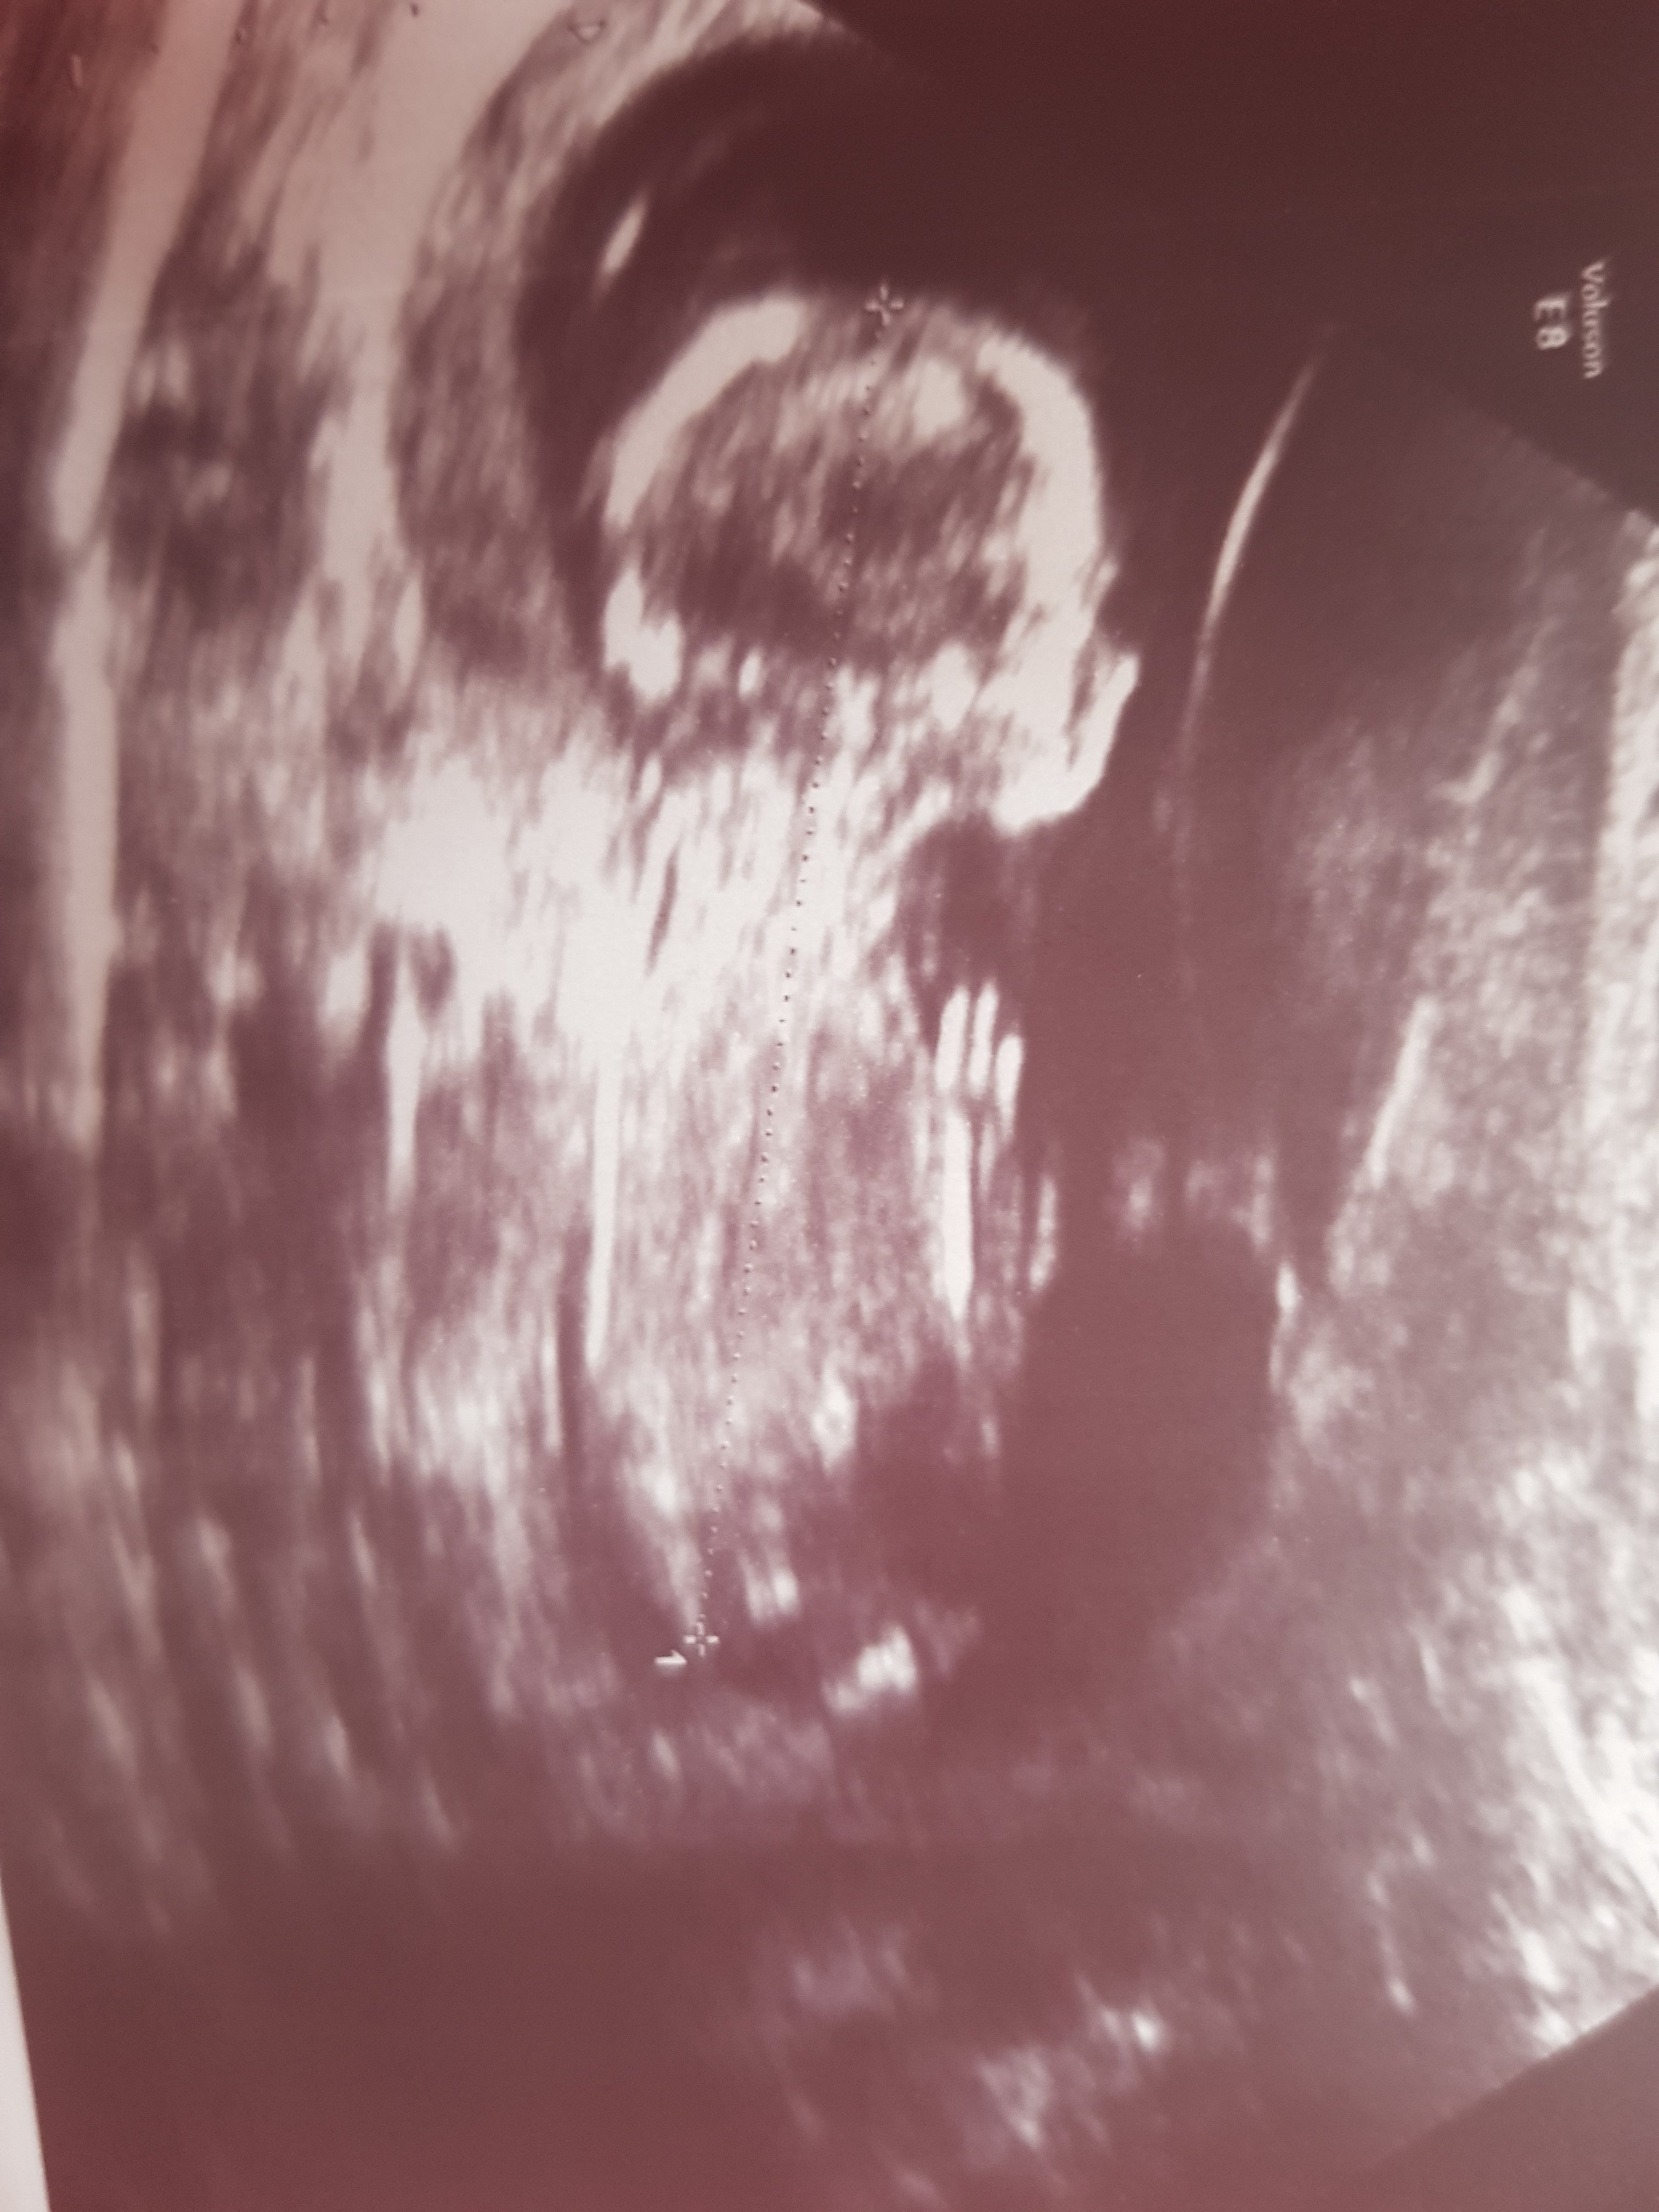

Rica etsem bi daha bakabilirmisiniz

• 15201187019731174839221.jpg

• Screenshot_20180223-203252.png

• Screenshot_20180223-202737.png

• Screenshot_20180223-202525.png